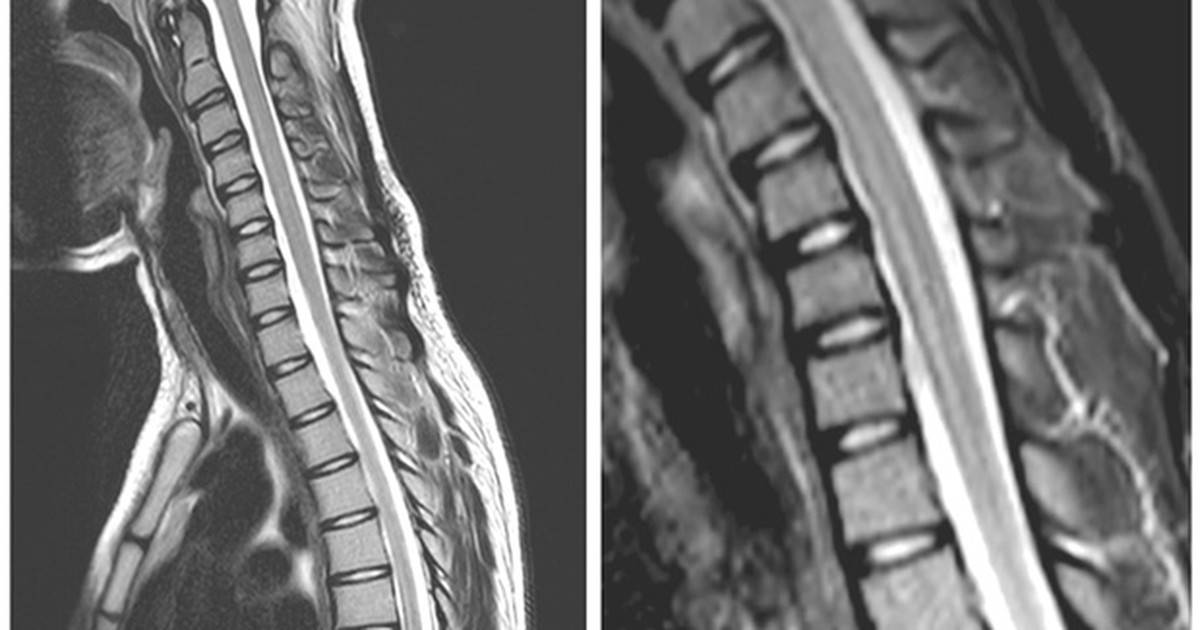

Заболевания миелит

Заболевания миелит 117 фото